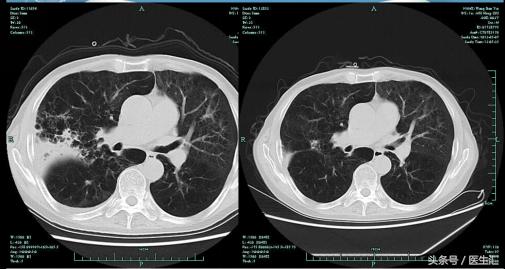

【肺CT】

【提示】该患者有COPD病史,但是本次住院有发热,肺CT上表现为右上肺后段及右下方基底段渗出实变病灶,因此应该考虑为肺炎,由于其在当地医院住院期间发生肺炎,因此诊断医院获得性肺炎

有COPD基础的患者,如果在原有疾病基础上,两肺出现新发的渗出实变病灶,诊断因考虑为肺炎,而不是AECOPD。如在住院期间发生肺炎,应诊断为院内获得性肺炎。该患者CT上病灶主要位于上叶后段及下叶基底段,考虑吸入性的可能性大。治疗上以碳青霉烯类抗生素或酶复合制剂为主